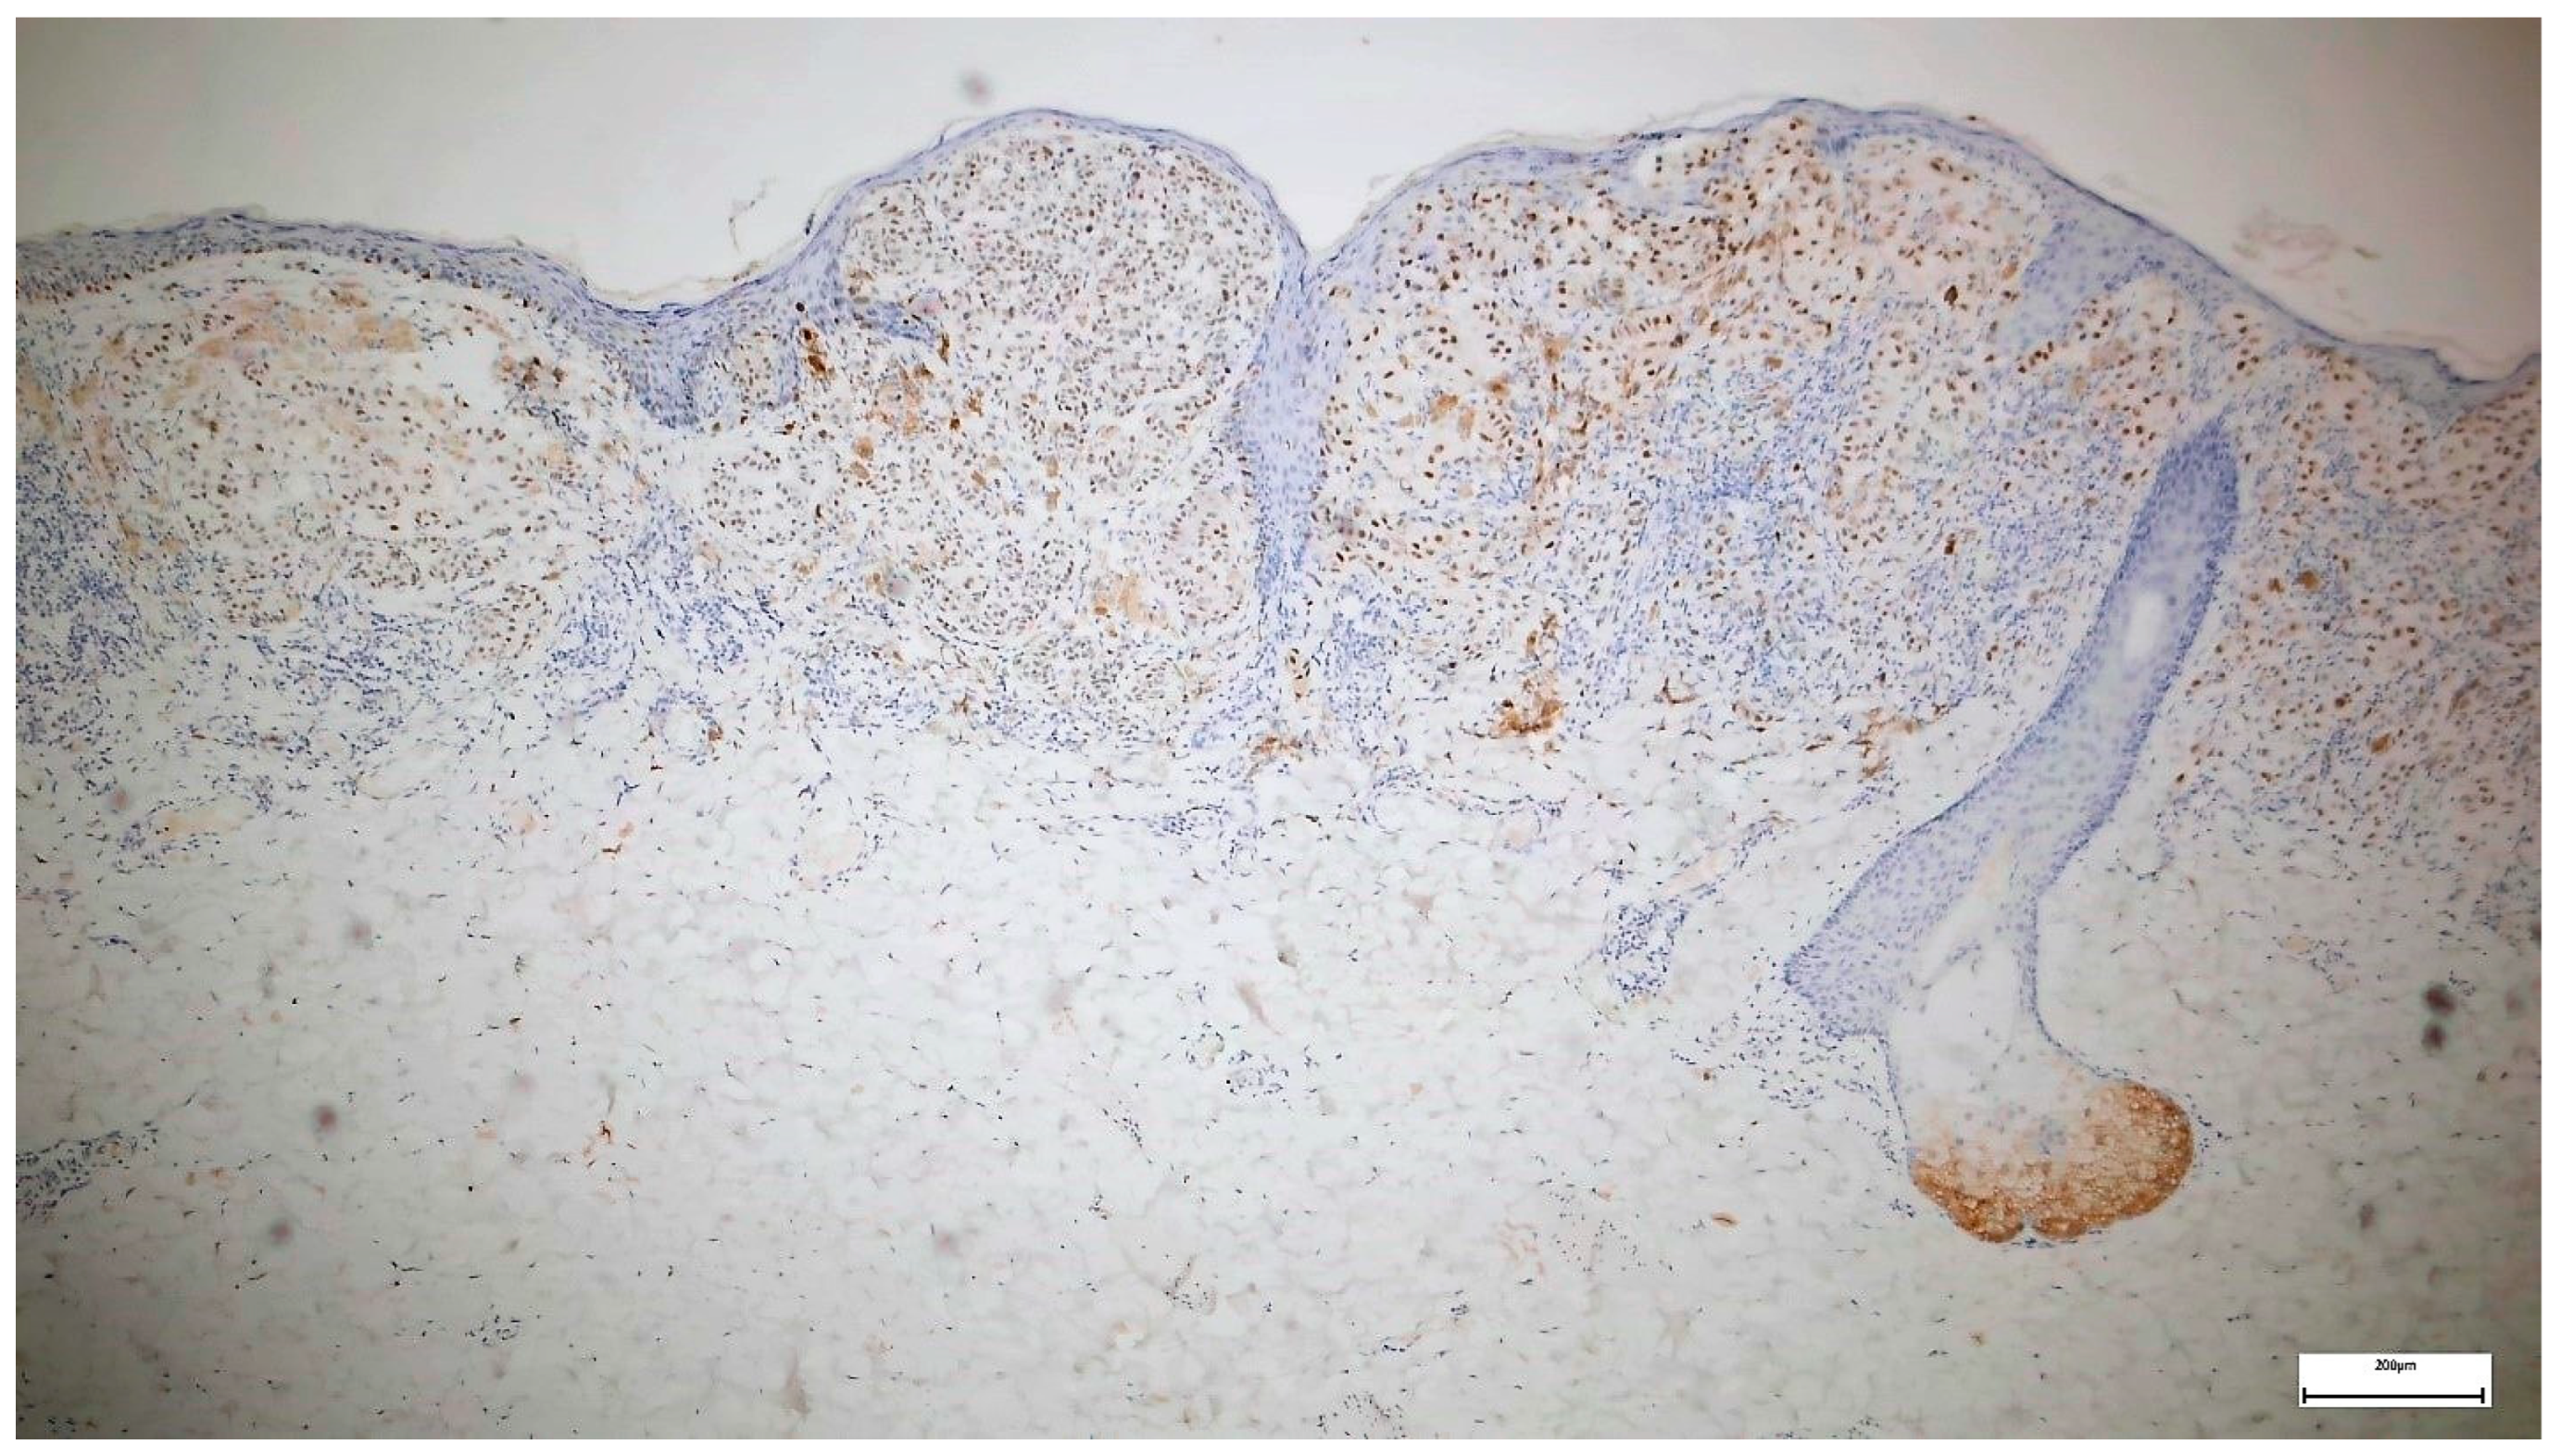

- Gassenmaier, M.; Hahn, M.; Metzler, G.; Bauer, J.; Yazdi, A.S.; Keim, U.; Garbe, C.; Wagner, N.B.; Forchhammer, S. Diffuse Prame Expression Is Highly Specific for Thin Melanomas in the Distinction from Severely Dysplastic Nevi but Does Not Distinguish Metastasizing from Non-Metastasizing Thin Melanomas. Cancers 2021, 13, 3864. [Google Scholar] [CrossRef]